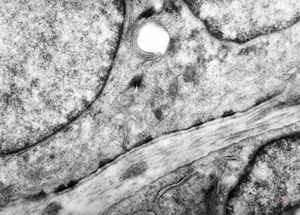

M, 1y. | epidermolysis bullosa … junctional type … rudimentary hemidesmosomes, missing anchoring fibrils